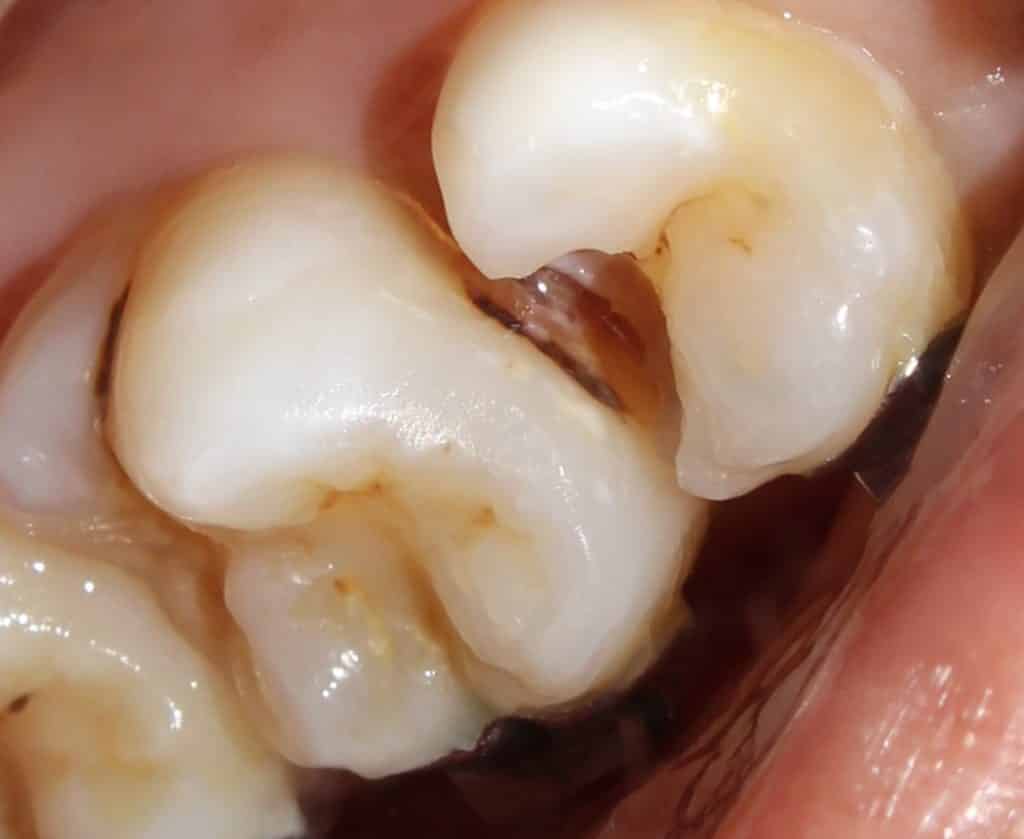

matrixing..

the completed work with amalgum done on 16 mesial.. and composites on all other cavities..